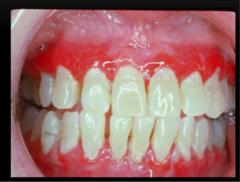

gingival enlagement

-Increase in the bulk of the free and attached gingiva with no stippling and erythmatous to normal color generalized or localized